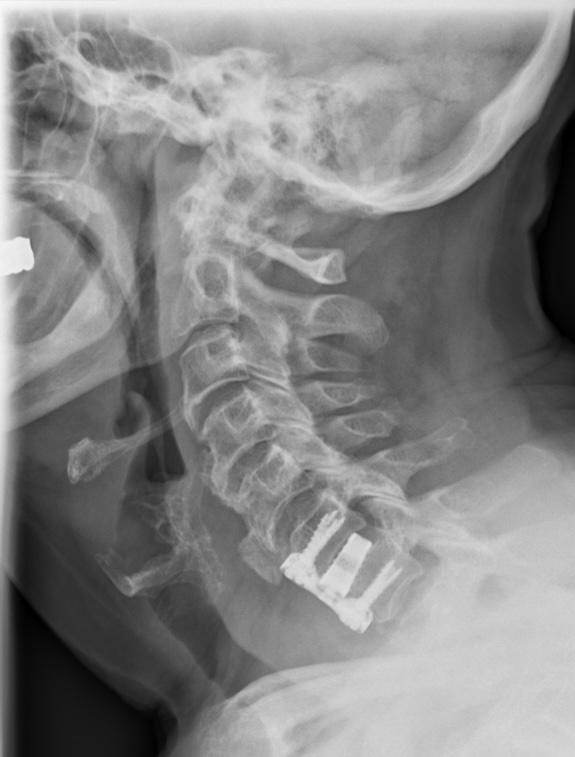

Das MRT zeigt eine 78 jährige Patientin. Schon seit Jahren klagt sie immer wieder über Nackenschmerzen. Seit einem halben Jahr hat sie ein Taubheitsgefühl in beiden Händen. Die Feinmotorik hat deutlich nachgelassen. So ist das Schliessen eines Hemdknopfes und dass Sticken nicht mehr möglich. Das Schriftbild ist kaum noch leserlich. Das Gehen ist sehr unsicher, vor allem bei Dunkelheit und auf unbekanntem Gelände.

Im MRT der HWS sieht man eine Einengung des Spinalkanals in Höhe des 6. und 7. Halswirbelkörpers. Im Spinalkanal verläuft das Rückenmark (dunkelgrau). In der Höhe der Stenose/Bandscheibenvorfalls  zeigt sich ein weisser Fleck innerhalb des Rückenmarkes. Das ist die „Myelopathie“ eine Schwellung bzw. Verletzung des Rückenmarkes aufgrund des Druckes.

Das 2. MRT Bild zeigt die Erweiterung und Entlastung des Kanals nach OP.

Im 3. Bild sieht man die Schrauben, Platte und Cage Stabilisierung in der Höhe HWK 6/7 zur Entlastung und Stabilisierung des Spinalkanals.

Direkt nach der OP waren die Beschwerden erst mal unverändert. Das Rückenmark braucht sehr viel Zeit, um sich zu erholen. Nach 6 Monaten (Zeitpunkt des 2. MRT Bild) war die Symptomatik gebessert aber immer noch nicht vollständig zurückgebildet.